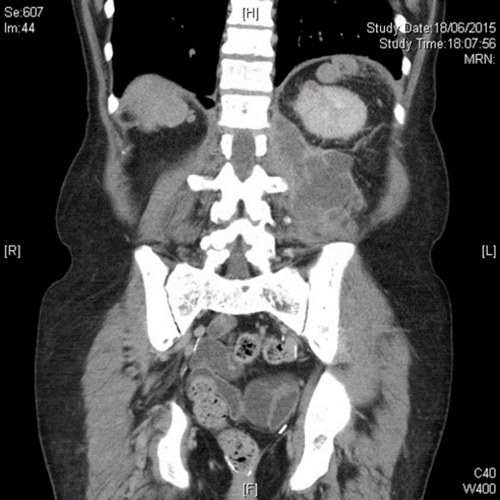

Case 1

An 80-year-old woman presented with history of recurrent and recent cystitis, low grade pyrexia, abdominal and back pain, and pain on movement of the left hip which was observed to be flexed and externally rotated.

- What is the diagnosis from the CT image?

- What are the usual sources of this infection?

- What are the principles of management?

-

Iliopsoas abscess. The classic triad of back pain, limp and fever may actually be present in only 30% of cases. Many patients have an insidious onset of non-specific symptoms and signs. The flexed and externally rotated hip is a consequence of irritation of the psoas muscle and referred pain from the nerve roots L2, L3 and L4 which supply the psoas muscle [1].

The known origins of secondary spread of infection to the iliac or psoas muscles may be broadly categorised into: a) Gastrointestinal (e.g. Crohn’s disease, diverticulitis, appendicitis, colorectal carcinoma); b) Genitourinary (e.g. urinary tract infections including pyelonephritis, instrumentation); c) Musculoskeletal infection (e.g. vertebral osteomyelitis, septic arthritis, infective sacroilitis); d) Others (endocarditis, trauma, femoral artery catheterisation, etc. Tuberculous infection has been implicated from both haematogenous spread and spread from adjacent TB focus, either skeletal, gastrointestinal or genitourinary).

First-line treatment is broad spectrum antibiotics that cover S. aureus (the most commonly isolated organism on cultures from aspirates). Surgical draining is the traditional treatment of choice with some authors describing quicker recovery after, although percutaneous drainage under imaging guidance is a good alternative. The latter may not be effective when small or multiple / multiloculated abscesses occur, or if access if difficult. A co-existing intra-abdominal disease requiring surgical intervention, such as complex Crohn’s disease or diverticulitis, may also determine which option is chosen. Small abscesses may be successfully treated with antibiotics alone [1].